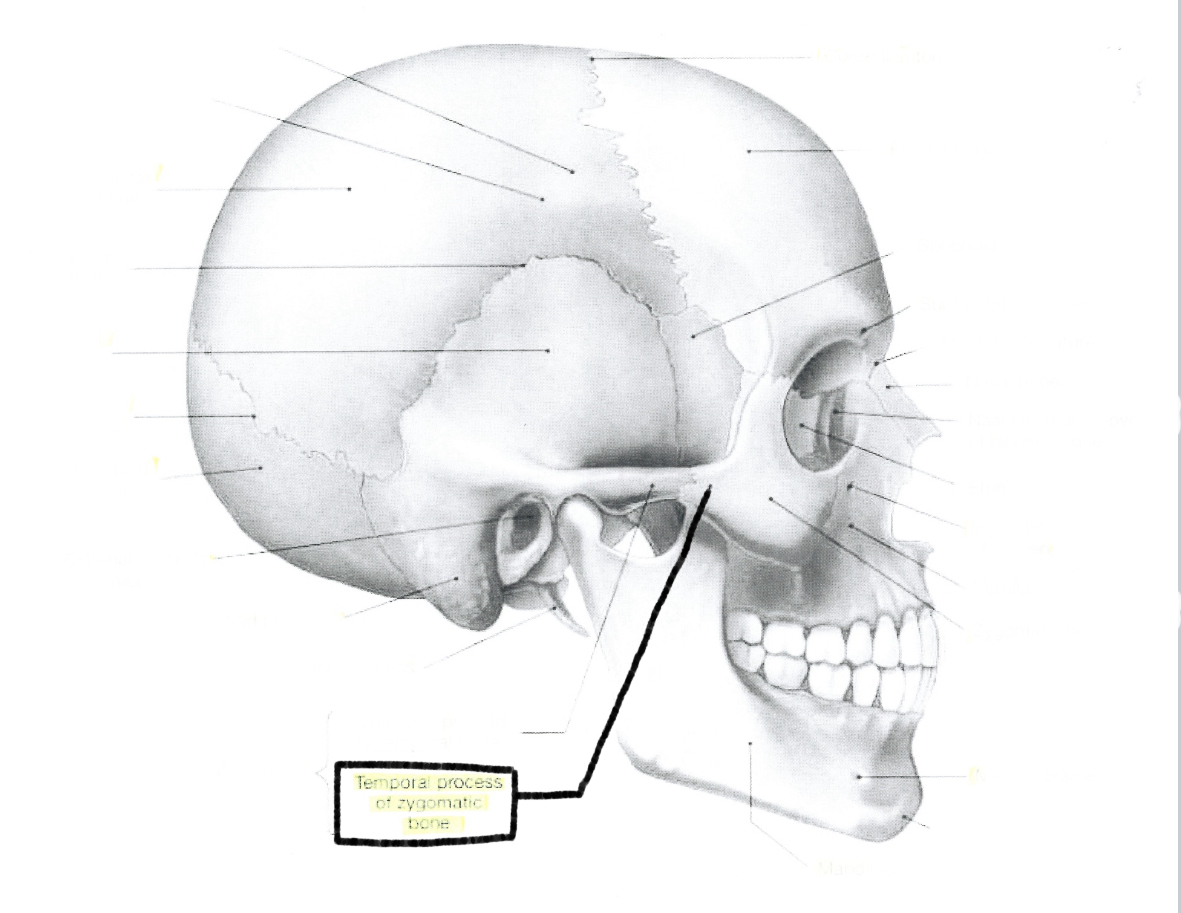

What is this?

Temporal process of zygomatic zone